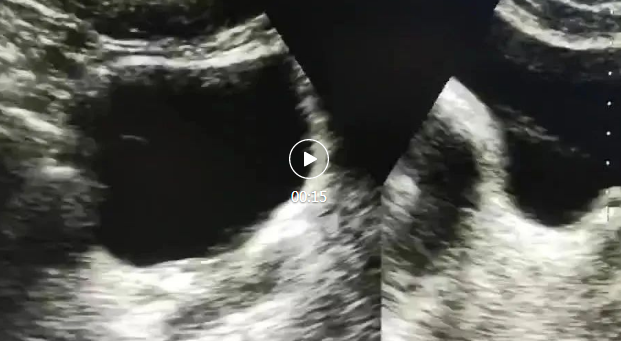

原来是在做体外冲击波碎石治疗(ESWL),它能利用高能冲击波将结石击碎,使其变成小颗粒,通过彩超定位可以观察到结石逐渐碎裂排入膀胱,随后通过尿液排出体外。视频中可见结石碎裂,一点一点排入膀胱,证明结石粉碎效果不错。

此图可看出结石变细变长,证明结石粉碎效果较好